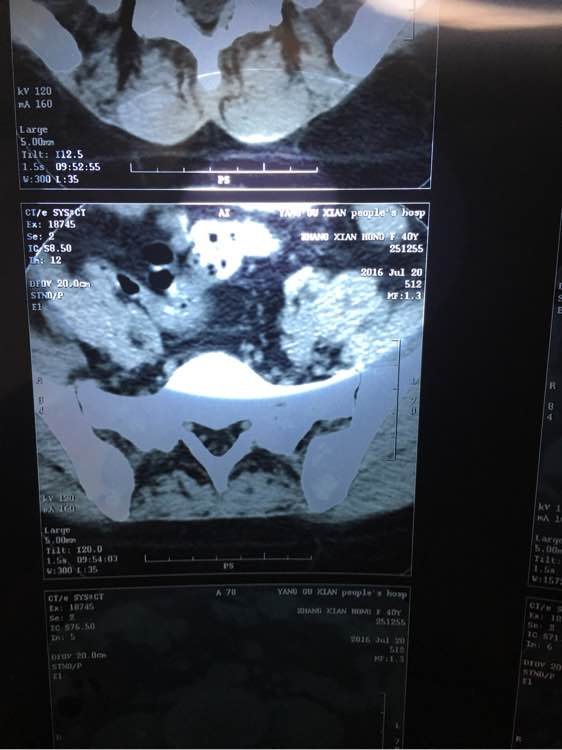

今天做了腰椎CT,却发现旁边有3个圆形黑点,特别明显,不知道是什么?内行的大神们给看下,拜托拜托了!